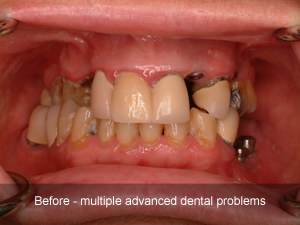

Clinical Cases